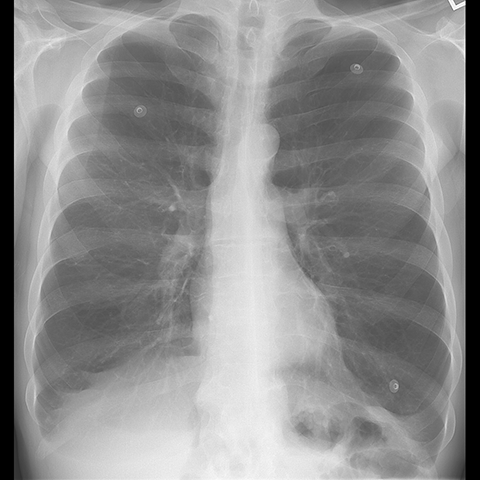

A 62 year-old male presents with chronic shortness of breath (Frontal Radiograph). [1 of 6]